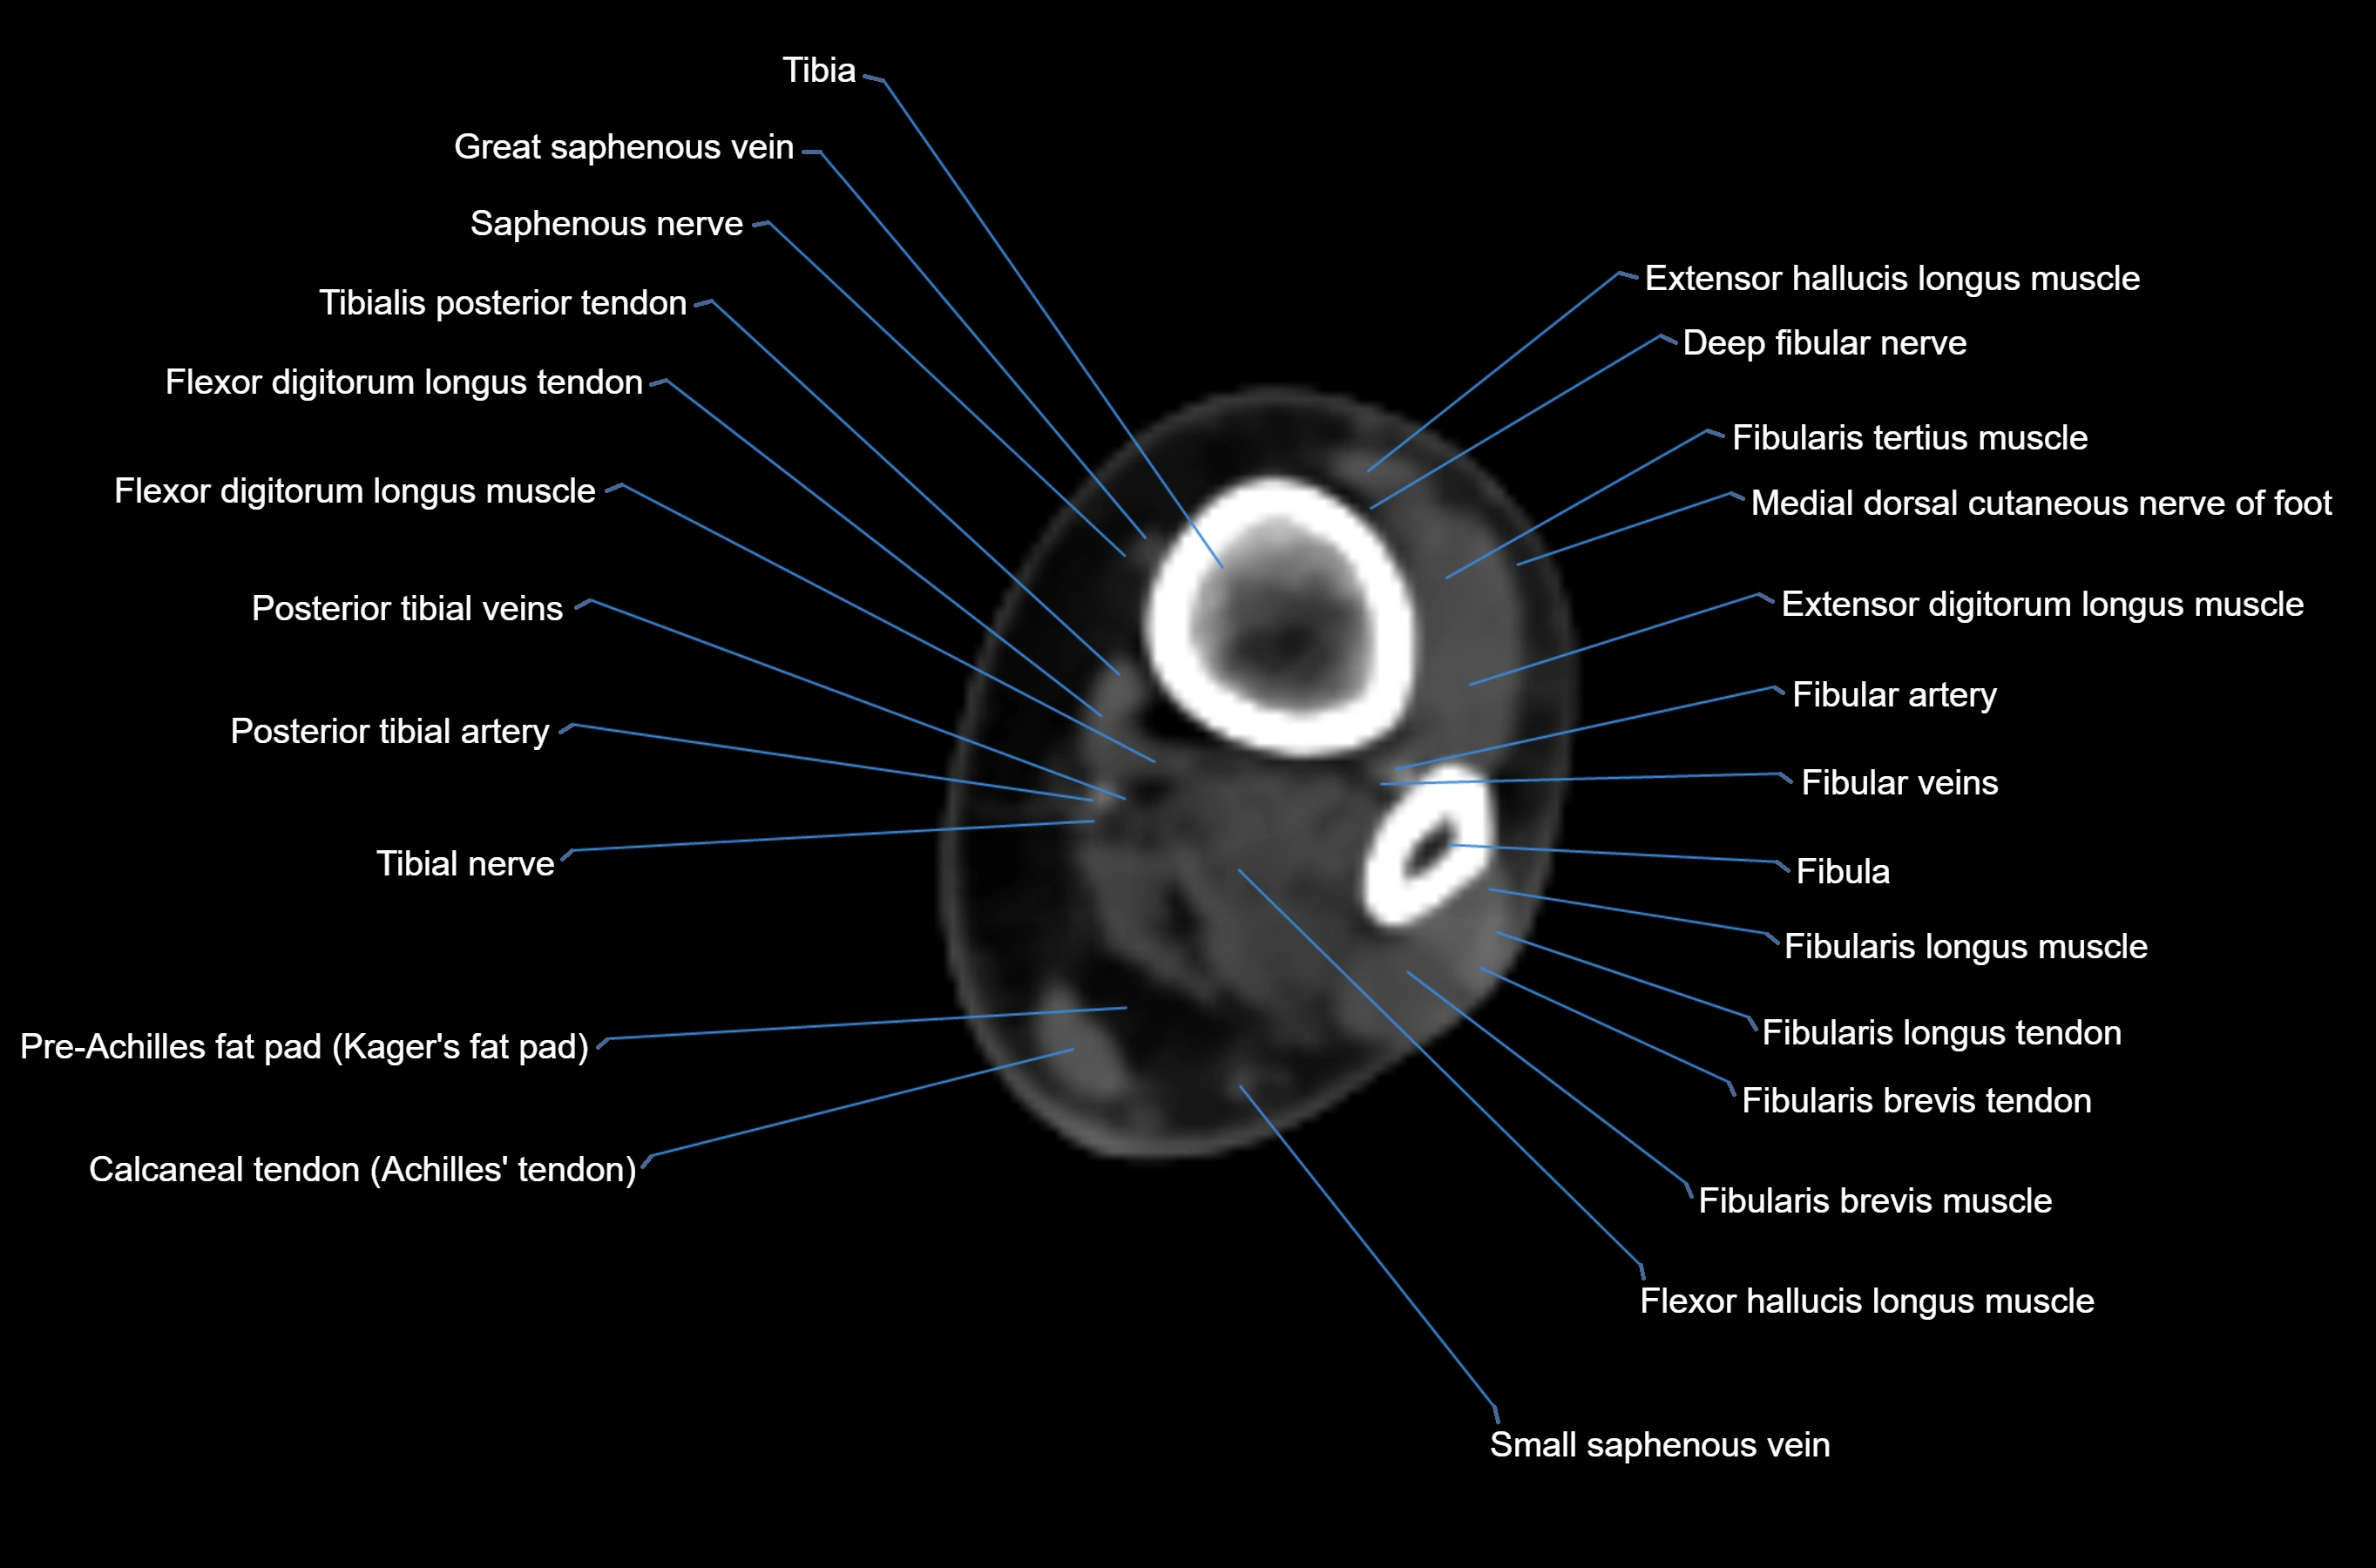

MRI image